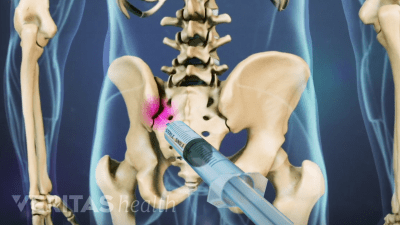

Discover the best radiographic tests for diagnosing SI joint dysfunction and ruling out serious medical conditions.

SI joint pain can last days to months and worsen if left untreated. Learn how to relieve SI joint pain quickly.